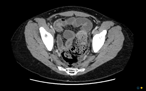

Endovascular intervention for iliac vein thrombosis after simultaneous kidney-pancreas transplant

Meredith Gunder and others

Journal of Surgical Case Reports, Volume 2019, Issue 4, April 2019, rjz024, https://doi.org/10.1093/jscr/rjz024